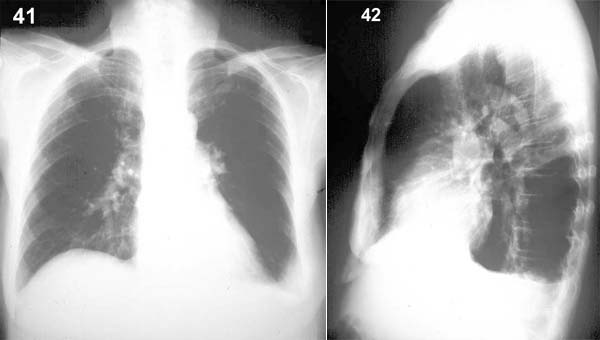

ESQUEMA 41 Comentario placas 41 y 42: En la radiografía frontal se aprecia que el ángulo costo frénico lateral izquierdo ha dejando de ser agudo y aparece ocupado o borrado por una sombra homogénea. En la placa lateral se ve el mismo fenómeno en relación al seno costo frénico posterior, donde se ha acumulado primero el líquido por su posición más baja. Pase a la placa 43 y describa sus hallazgos |